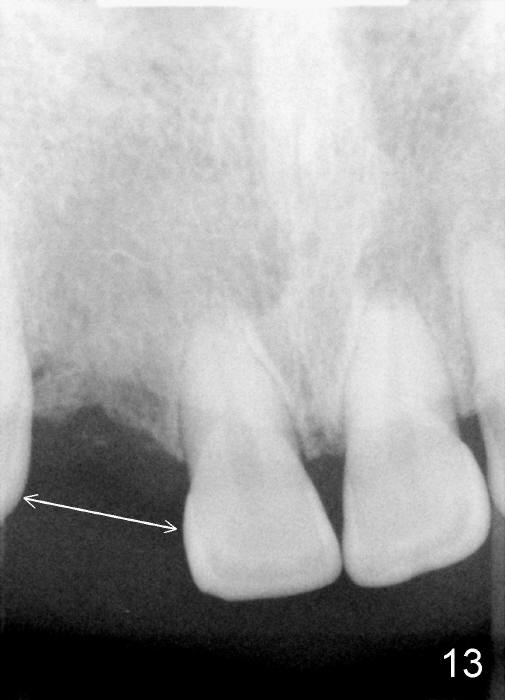

Preop PA shows that the edentulous space is extraordinarily wide mesiodistally (Fig.13 double arrows). There should be enough room to place osteotomy lateral to the implant (3.8x14 mm, Fig.14, immediately post placement).